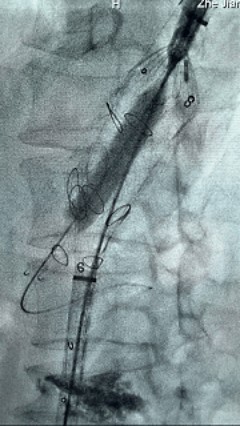

8. 从右侧股动脉入路送入腹主支架AB-24-12-110-S,近端重叠胸腹主动脉支架远端,调整好支架位置后释放。

9. 经左股动脉送入导丝导管,超选进腹主动脉支架短腿内,后沿导丝送入髂支,同理,右侧沿导丝送入髂支并释放,使用先健顺应性球囊后扩各支架连接处及支架近远端,最后通过预留导管向瘤腔注入人纤维蛋白粘合剂数支,造影显示分支通畅。

19.gif

术后评价

G-Branch在本例手术中展现出对扭曲解剖结构的出色适应性,针对该患者严重扭曲的瘤颈,支架系统的优异柔顺性使其能够顺利通过复杂路径,完成内脏分支血管的重建。

其独特的双内嵌、双外翻混合多分支设计兼顾了操作效率与结构可靠性,预置导丝系统简化了肠系膜上动脉(SMA)和腹腔干动脉(CA)的超选流程,显著提高手术效率。